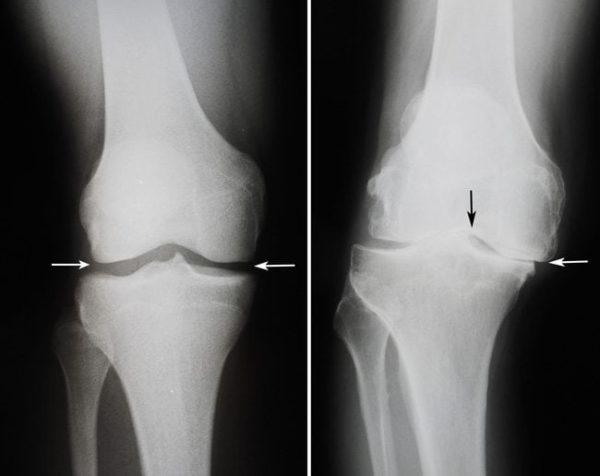

Это разрушение хрящевой ткани в коленном суставе и образование остеофитов, то есть костных наростов. Артроз приводит к деформации, сужению суставной щели и образованию анкилоза. Постепенно, если не проводить лечение, щель между суставами полностью исчезает, и подвижность сустава теряется.

Артроз может развиваться у людей любого возраста. На начальном этапе заболевание протекает незаметно, и боль ощущается лишь после значительных физических нагрузок, после чего она проходит самостоятельно.

На второй стадии болевые ощущения становятся постоянными, и человеку требуется принимать обезболивающие и противовоспалительные препараты. Из-за боли амплитуда движений в колене значительно уменьшается.

На последней стадии происходит полное разрушение хрящевой ткани. Пациент страдает от постоянных болей и теряет возможность нормально передвигаться, в данной ситуации единственным решением может стать операция.

Проблемы с коленом могут мешать многим: от занятий спортом до простого вставания со стула и ходьбы. Это может существенно повлиять на вашу жизнь. Наиболее распространённым заболеванием колена является остеоартрит. Хрящ в колене постепенно изнашивается, вызывая боль и отёк.

Гонартроз – это артроз коленного сустава, хроническое невоспалительное заболевание, проявляющееся прогрессирующим разрушением внутрисуставного хряща, которое сопровождается аномальным формированием костей, образующих сустав, изменениями синовиальной оболочки и синовиальной жидкости.